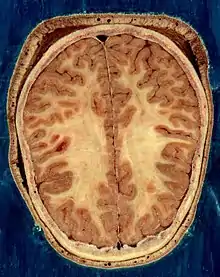

Cortical folds and white matter in horizontal bisection of head

The cerebrum contains the ventricles where the cerebrospinal fluid is produced and circulated. Below the corpus callosum is the septum pellucidum, a membrane that separates the lateral ventricles. Beneath the lateral ventricles is the thalamus and to the front and below is the hypothalamus. The hypothalamus leads on to the pituitary gland. At the back of the thalamus is the brainstem.[26]